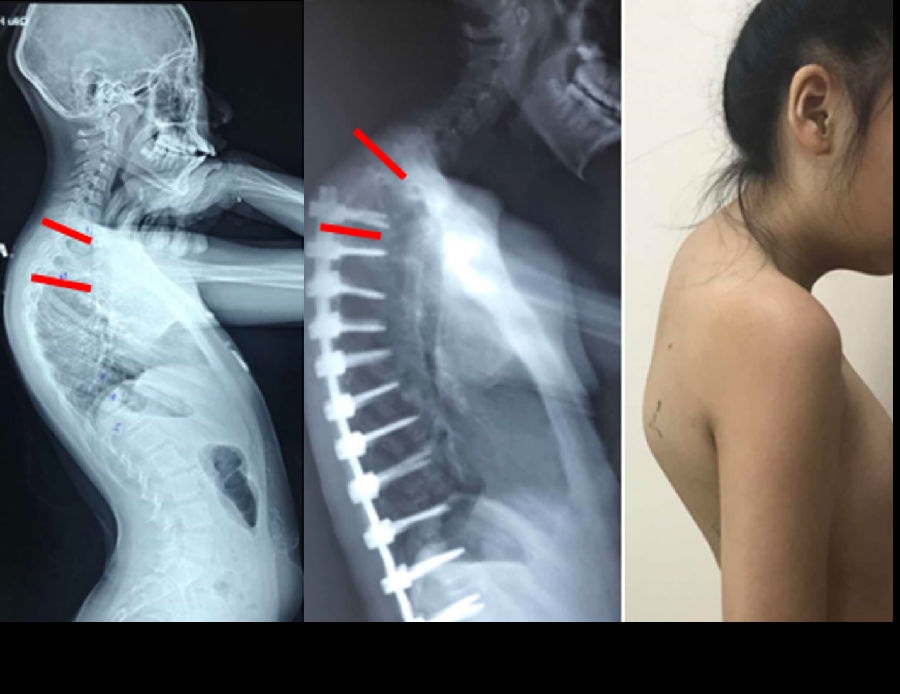

(2)上固定椎在交界区或存在交界性后凸

图6 长节段融合固定上固定椎(UIV)选择在胸10-12胸腰椎交界区是PJK的风险因素之一